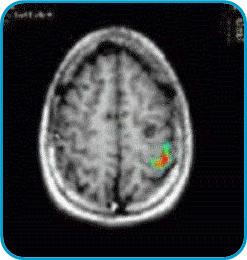

En la imagen izquierda hay un pequeño quiste en el hemisferio izquierdo (nótese en el lado derecho del cerebro como un redondel negro). Esta lesión producía convulsiones. El cirujano necesitaba saber qué parte de la corteza estaba a cargo del movimiento de la mano. Con movimientos alternos de los dedos, esta imagen de resonancia magnética funcional muestra a color el área usada para el movimiento de los dedos de la mano derecha. Esto le permite al cirujano extirpar la lesión sin afectar el movimiento de la mano.